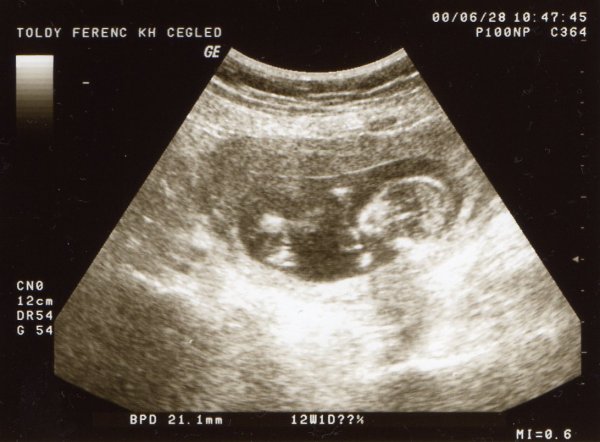

Saxi, Mica! Gratulálok a kis pocaklakókhoz és nagyon jó egészséget, boldog pocakosodást kívánok nektek!!!!